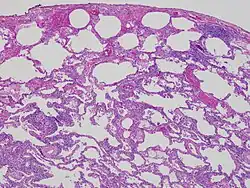

Esta es una fotomicrografía a gran aumento de una biopsia pulmonar (tinción hematoxilina-eosina). Muestra una moderada expansión de los tabiques alveolares (intersticio) debida a linfocitos. Una célula gigante multinucleada, vista dentro del intersticio a la derecha de la imagen medio camino hacia abajo, es una pista importante hacia el diagnóstico.

Vista a pequeño aumento de la histología de la alveolitis alérgica extrínseca (material de biopsia pulmonar). El intersticio está expandido por un infiltrado inflamatorio crónico. Dos células gigantes multinucleadas pueden ser vistas dentro del intersticio a la izquierda, y un tapón de neumonía organizada abajo a la izquierda.